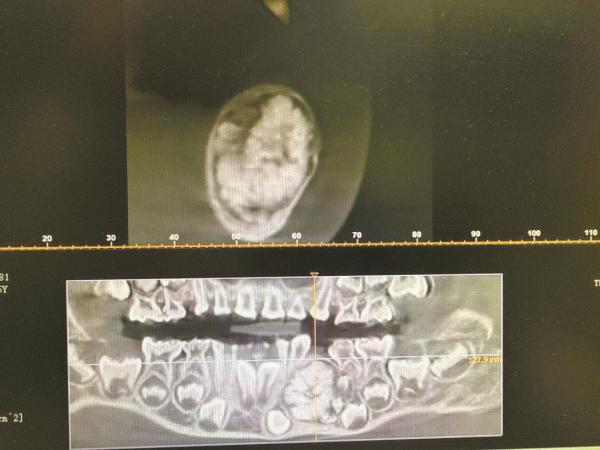

颌面部CT检查结果一出来,瑞瑞父母面面相觑:影像画面中,瑞瑞颌骨的病变区域内,细小牙体组织层层簇拥、密密麻麻,像一团被紧紧捏实的小石子,几乎填满了局部骨腔。

成年人口腔中的牙齿数量通常为28颗至32颗,但瑞瑞的颌骨里竟然藏着40余颗“小牙齿”。徐斌团队为瑞瑞成功实施全麻手术,从其颌骨内摘除了这团密密麻麻的良性牙瘤。